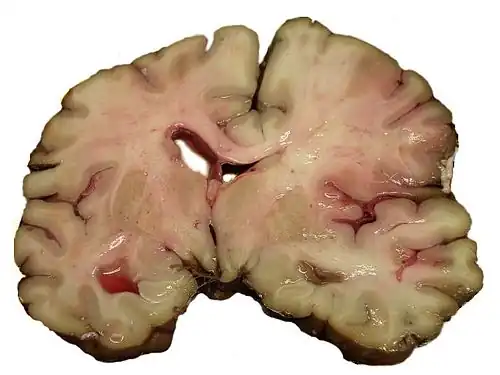

Emorragia intracerebrale

Si verifica, in genere, nelle piccole arterie o arteriole del cervello ed è spesso causata dall'ipertensione,[42] da malformazioni vascolari intracraniche (compresi emangiomi cavernosi o malformazioni artero-venose), da angiopatia amiloide o infarti cerebrali in cui si è verificata una emorragia secondaria.[2] Altre cause possibili sono traumi, disturbi emorragici, angiopatia amiloide, consumo di sostanze stupefacenti (ad esempio, anfetamina o cocaina). L'ematoma formatosi si allarga fino a quando la pressione dal tessuto circostante limita la sua crescita o fino a quando non si decomprime svuotandosi nel sistema ventricolare o nel liquido cefalorachidiano. Un terzo delle emorragie intracerebrali si verifica nei ventricoli cerebrali, con un tasso di mortalità del 44% dopo 30 giorni, un valore superiore all'ictus ischemico o all'emorragia subaracnoidea (che tecnicamente può anch'essa essere classificata come un tipo di ictus[2]).